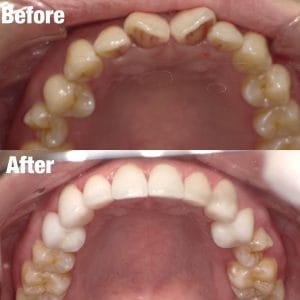

Case009

前医でマウスピース矯正をしたものの、うまくいかなくて当院にお越しくださった患者様です。

もう時間をかけたくないとの主訴だったので、マウスピース矯正ではなくセラミック矯正で治しました。

クリーニング+セラミック矯正+ホワイトニング

来院回数 3回(初回のカウンセリング含む)

初診時よりとても綺麗になって満足して頂きました。

担当:理事長 佐藤悠野